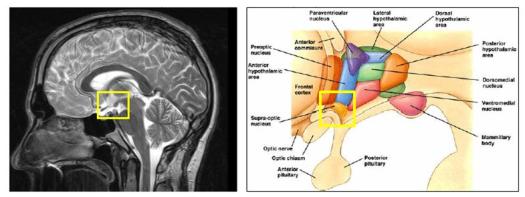

Hoy, vamos a agregar un ingrediente más, en este peculiar programa de cocina cerebral, una estructura similar a un guisante (algunos científicos hablan del formato de pera muy pequeña ó de San Juan), con un peso de 0.5 gramos, que se denomina científicamente glándula pituitaria (también conocida como hipófisis, “crecimiento inferior”) y que se aloja en un espacio óseo, la silla turca, del hueso esfenoides, situada en la base del cráneo, en la fosa cerebral media, que conecta con el hipotálamo a través del tallo pituitario o tallo hipofisario. La etimología es sumamente curiosa para comprender anatómicamente esta microestructura de extraordinaria importancia en las mujeres y hombres, por este orden. Pituitaria significa que contiene o segrega pituita, del latín “pituita”: secreción, fluido, moco, flema, formando parte de la medicina tradicional junto a los tres “humores” restantes: sangre, bilis amarilla y bilis negra. Es una superestructura del sistema endocrino dado que ejerce un control férreo sobre ocho glándulas endocrinas que explicamos a continuación.

Esta glándula está unida al hipotálamo a través de fibras nerviosas y está formada por tres secciones: el lóbulo anterior, que representa el 80% del peso de la glándula, el lóbulo intermedio y el lóbulo posterior. El lóbulo anterior produce la hormona de crecimiento, la prolactina, que estimula la producción de leche materna después de dar a luz, la adrenocorticotrópica (ACTH), que estimula las glándulas adrenales, la estimulante de la tiroides (TSH), que estimula la glándula tiroides, la folículo-estimulante (FSH), que estimula los ovarios y los testículos al igual que la luteinizante (LH), también presente.

El lóbulo intermedio, produce la hormona estimulante de melanocitos que controla la pigmentación de la piel. El lóbulo posterior, produce la hormona antidiurética (ADH), que aumenta la absorción de agua en la sangre por medio de los riñones. Igualmente, la oxitocina, que contrae el útero durante el parto y estimula la producción de la leche materna.

Esta supercentral hormonal cumple unas funciones determinantes en el ser humano. Louann Brizendine, la autora revelación sobre el cerebro femenino, sitúa la glándula pituitaria como sexta estructura que lo caracteriza: “produce las hormonas de la fertilidad, producción de leche y comportamiento de crianza. Ayuda a poner en marcha el cerebro maternal”. Además, en el salto de la pubertad se desencadena la propulsión de las células hipotalámicas y la niña-mujer comienza a experimentar cambios que ya se repetirán día a día, mes a mes hasta la menopausia, porque “la glándula pituitaria… salta a la vida cuando los frenos químicos se sueltan en las células hipotalámicas […]. Esta liberación celular dispara el sistema hipotalámico-pituitario-ovárico” (1). El conocimiento de esta realidad recurrente en la vida de la mujer debe ayudar a los hombres a respetar íntegramente estos ciclos vitales que producen desajustes vitales, por responsabilidad directa de la naturaleza al estar muy desarrollada esta glándula en la mujer en el lóbulo anterior de la misma (recuerdo que el peso específico de esta zona desarrolla el 80% de su función diaria y perfectamente programada). No ocurre lo mismo en el cerebro masculino, porque el balanceo hormonal no pasa tanta factura en la vida ordinaria. Si se conoce bien esta estructura, se respeta. Además, se pueden poner ejemplos rotundos de este “conocimiento” cerebral femenino, basados en una hormona bastante desconocida a nivel popular pero que juega un papel trascendental en la mujer y en las relaciones de pareja. Me refiero a la oxitocina, una hormona muy atractiva para el objeto de estas publicaciones.